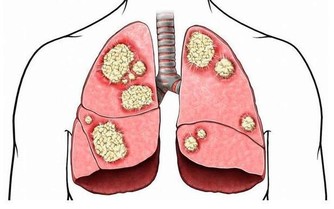

4、常吃豬血湯豬血中的血漿蛋白,經過人體胃酸和消化液中的酶分解後,會產生一種解毒和滑腸作用的物質,與侵入胃腸的粉塵、有害金屬微粒發生化學反應,變為不易被人體吸收的廢物。5、常吃菌類植物黑木耳和菌類植物有良好的抗癌作用,並且能清潔血液和解毒,經常食用能有效清除體內污物。這些是具有排毒功能的食品,能夠幫助清理體內垃圾,常吃很有好處。

功效:苦瓜含有一種具有明顯抗癌功效的活性蛋白質,能夠激發體內免疫系統防禦功能,增加免疫細胞活性,清除體內有害物質。

適合症狀:茶有明顯的防癌抗癌作用,堅持飲茶有防止腫瘤產生的積極功效